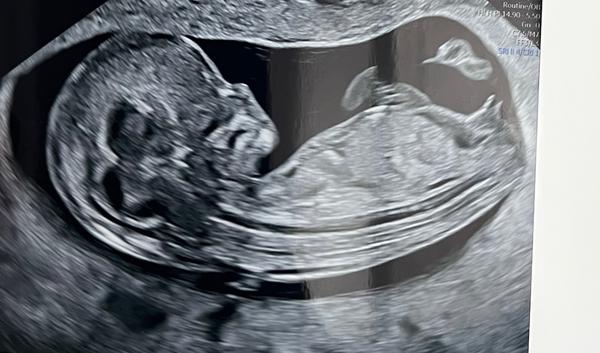

Ahojteee dnes som bola na prvotrimestralnom skríningu v Martine u Dr.Grochala a nevedel ešte určiť pohlavie bábätka že je to tak 50/50. Ja som však veľmi zvedava a chcela by som sa opýtať ak “to” malo vaše babatko v rovnakom smere aké to bolo nakoniec pohlavie?🙂) alebo čo tipujete u mna?😃

Druha je nase babatko